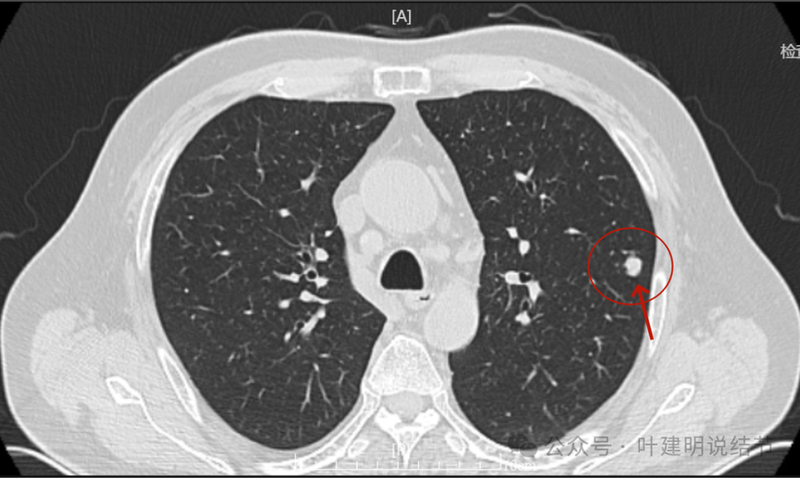

回顾看2023年10月时左上叶此处略有异常,微小实性结节,有血管与之相连。

2024年1月病灶较3个月前明显增大进展,是实性小结节,有微小血管走向病灶。